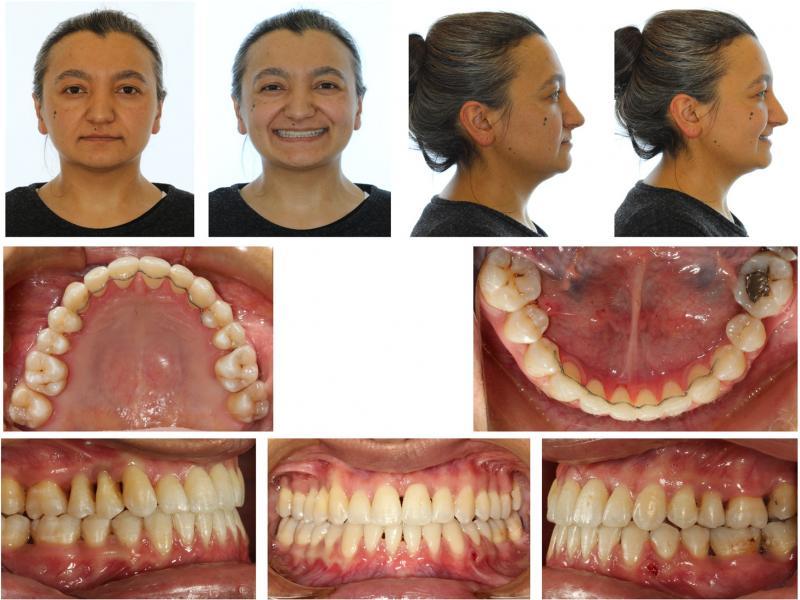

Figure 1.